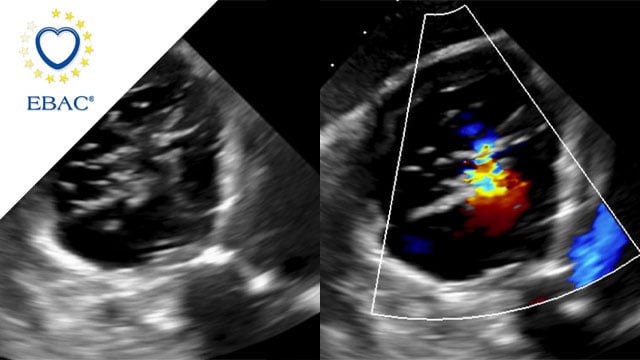

How should I treat a torrential tricuspid valve regurgitation in a young patient who remains symptomatic despite optimal medical therapy?

How should I treat a torrential TR in a young patient who remains symptomatic despite OMT?

A frail patient presents with worsening NYHA class III dyspnoea and peripheral oedema despite optimal medical therapy...